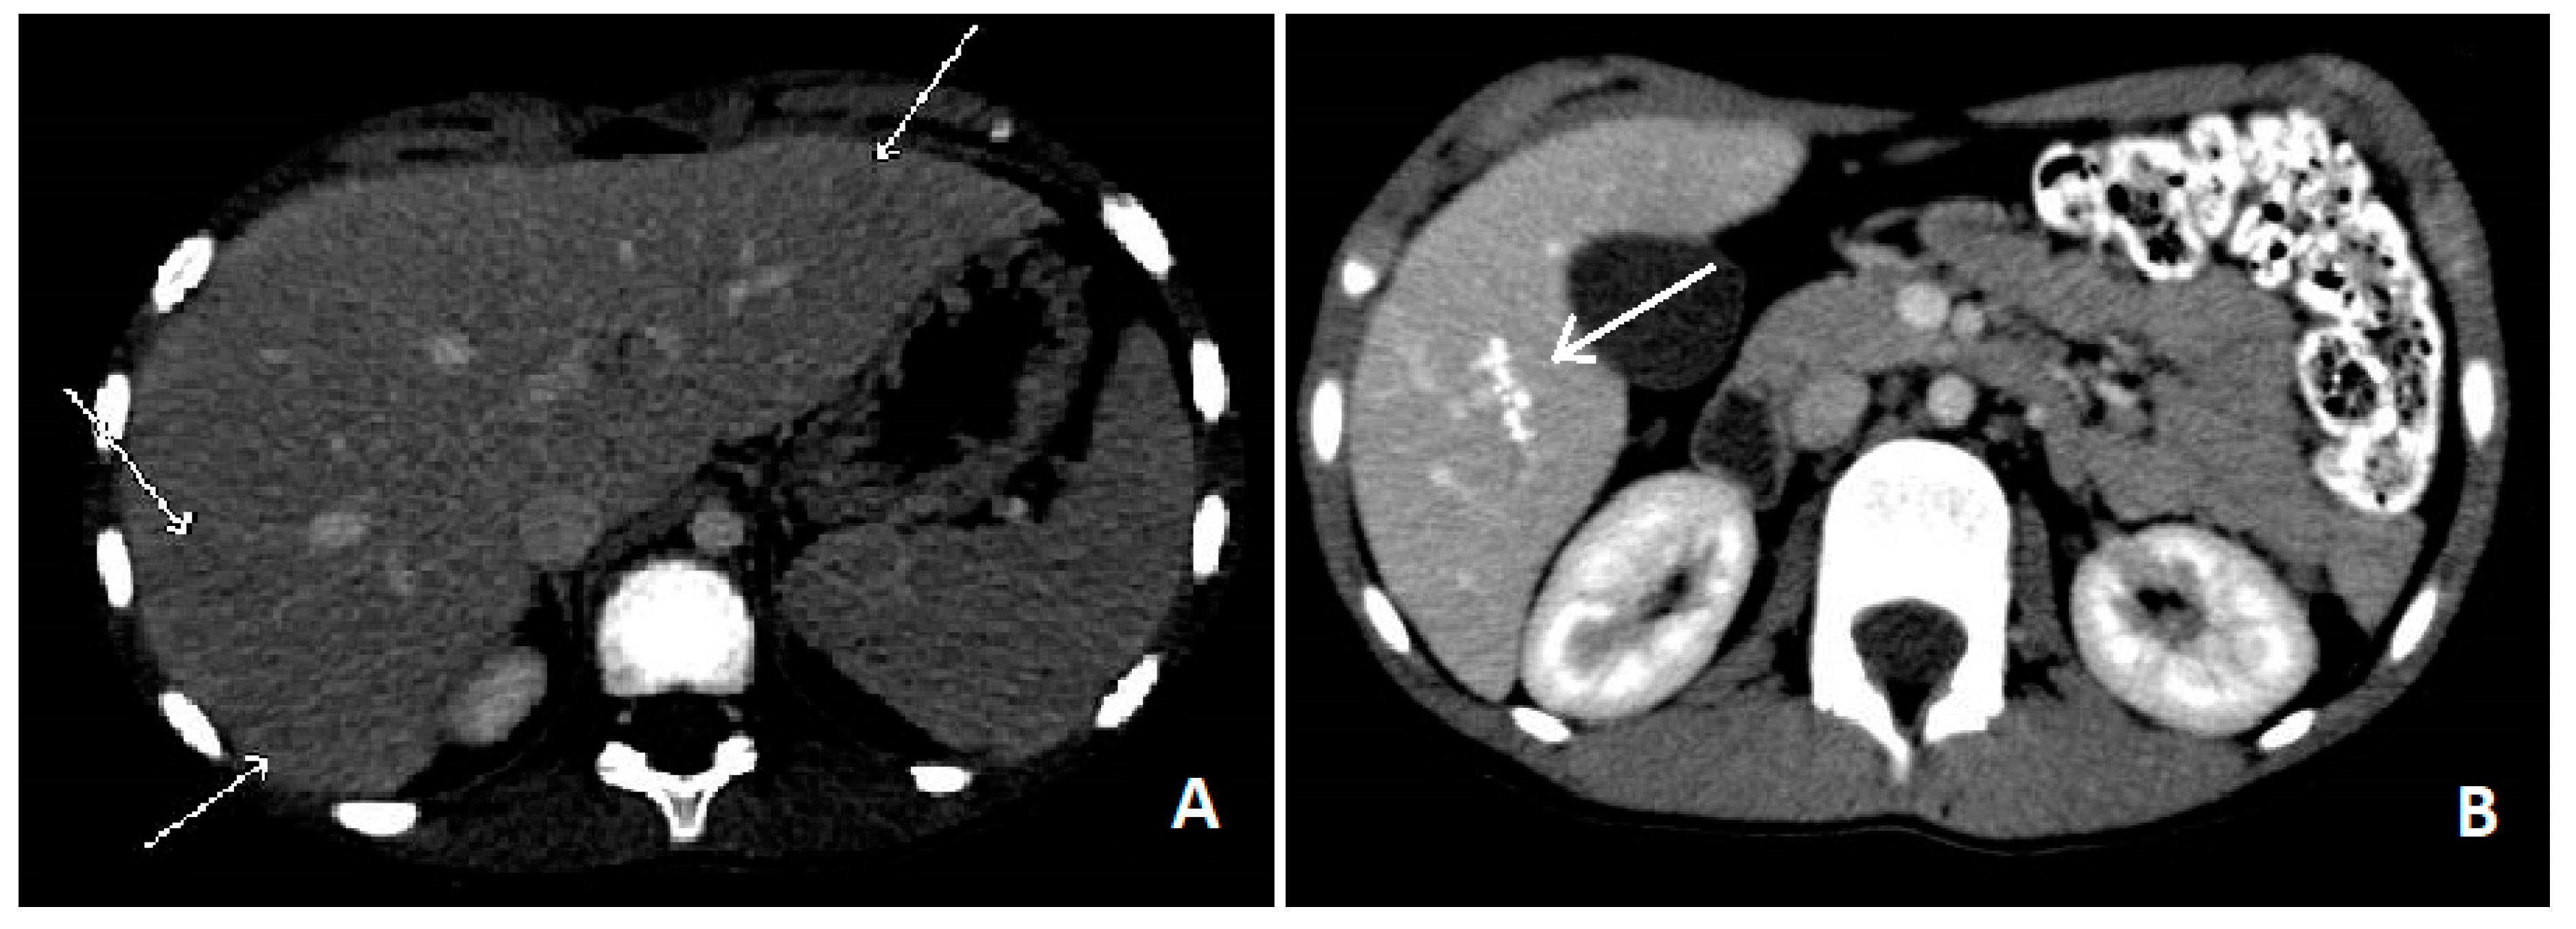

Blood tests showed leucocytosis (36,270/mcL) with severe eosinophilia (26,220/mcL), slight increase of ESR (39 mm/h) and RCP (1.26 mg/dL), hypergammaglobulinemia and high levels of IgG (2370 mg/dL) IgM (236 mg/dL) and total IgE (4980 U/mL). No blasts were found on the peripheral blood smear, ruling out blood diseases. Liver function test, creatinine, glucose and electrolytes were normal. An upper abdominal echography revealed multiple small (less than 10 mm) hypoechoic nodules all over the liver, with some reactive periportal lymph nodes. To confirm these findings, we performed an abdominal computed tomography (CT), which showed hypodense lesions with softly hyperdense peripheral haloes, located in IV, V and VI hepatic segments and sub-centimetre lesions in the left hepatic lobe (see

Figure 1A). Chest X-ray examination did not show any involvement of the lungs, but a thoracic CT revealed multiple parenchymal nodules (up to 6.5 mm), located in the peripheral basal segments of the inferior left and the right posterior pulmonary lobes.

Figure 1B).